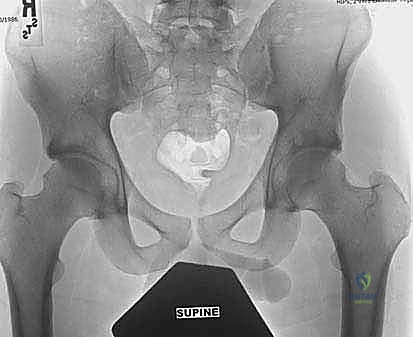

- الأشعة السينية الرقمية (X-Rays): أخذ زوايا محددة (مثل Dunn View و Cross-table lateral) لقياس زاوية ألفا (Alpha Angle) وتحديد حجم التشوه العظمي.

- الأشعة المقطعية ثلاثية الأبعاد (3D CT Scan): في الحالات المعقدة، يتم بناء نموذج ثلاثي الأبعاد لورك المريض، مما يسمح للدكتور هطيف بالتخطيط الجراحي المسبق ومعرفة مقدار العظم الذي يجب إزالته بدقة المليمتر.